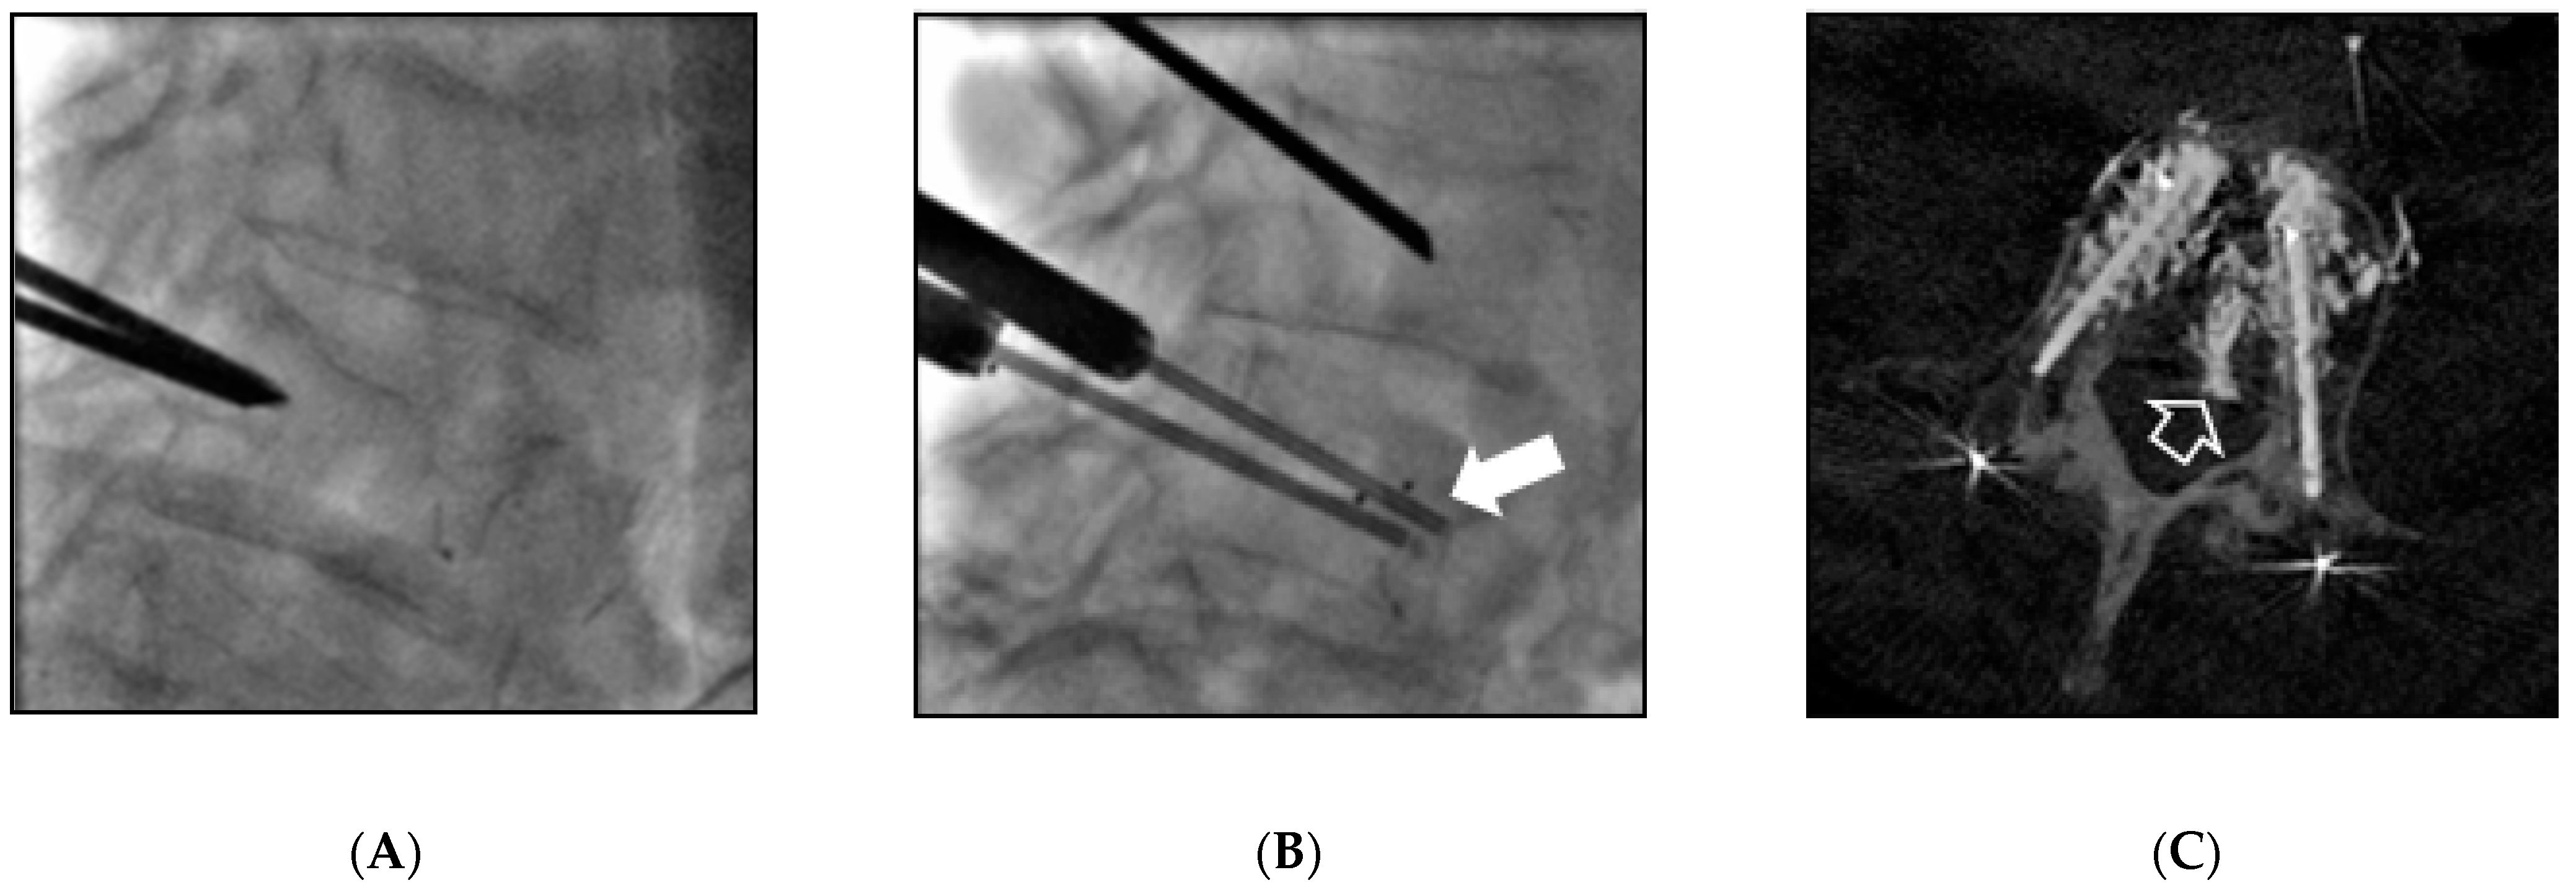

| 1 | 59 | Female | Breast | L2 | 10 | V-strut® (2) | Electrochemotherapy | L2 | Cement leakage (1) | - |

| 2 | 53 | Female | Breast | L4 | 8 | V-strut® (2) | - | - | - | - |

| 3 | 64 | Male | Lung | L2 | 9 | V-strut® (2) | Vertebroplasty | L3 | VCF L4&L5 (2) Cement leakage (1) | Vertebroplasty |

| 4 | 58 | Male | Lung | L4 | 9 | V-strut® (2) | - | - | Cement leakage (1) | - |

| 5 | 54 | Female | Breast | L4 | 10 | V-strut® (2) | Vertebroplasty | L3 | VCF L5 (2) Cement leakage (1) | - |

| 6 | 48 | Male | Lung | L1&L4 | 9 | SpineJack® (4) | Vertebroplasty | T9 T10 T11 T12 | - | - |

| 7 | 62 | Male | Lung | L3 | 9 | SpineJack® (2) | Vertebroplasty | T2 T3 T4 | - | - |

| 8 | 40 | Female | Breast | T8 | 7 | SpineJack® (2) | - | - | - | - |

| 9 | 73 | Female | Breast | L1 | 10 | SpineJack® (2) | - | - | VCF L2 (3) Cement leakage (1) | Spinejack® (2) |

| 10 | 56 | Female | Ovarian | T12 | 12 | SpineJack® (2) | Vertebroplasty | T10 T11 L1 | - | - |

| 11 | 79 | Female | Lung | L1&L2 | 01 | SpineJack® (4) | - | - | - | - |

| 12 | 23 | Female | Osteosarcoma | T12&L1 | 9 | SpineJack® (2) | Vertebroplasty | C7 T3 T5 | Cement leakage (1) | - |

| 13 | 89 | Female | Ovarian | T11&L1 | 10 | SpineJack® (2) | Vertebroplasty | T12 | - | - |

| 14 | 74 | Female | Ovarian | T12&L1 | 10 | SpineJack® (4) | Vertebroplasty | L2 | Cement leakage (1) | - |

| 15 | 59 | Female | Breast | T9 | 9 | Kiva® (1) | - | - | - | - |

| 16 | 57 | Male | Myeloma | L2 | 7 | Kiva® (1) | - | - | - | - |

| 17 | 78 | Male | Lung | T12 | 7 | SpineJack® (2) | Vertebroplasty | T3 T4 | - | - |

| 18 | 49 | Female | Breast | T10 | 7 | Spinejack® (2) | - | - | - | - |